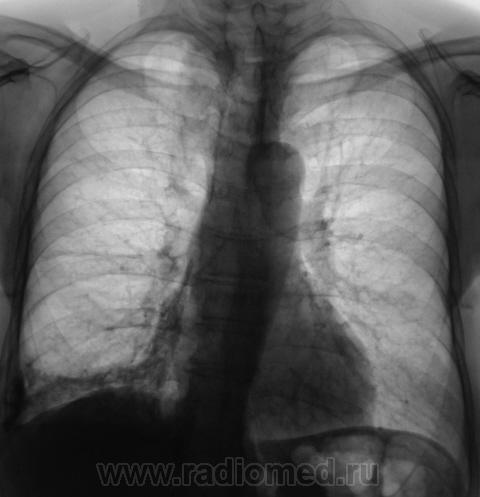

Пациент направлен на рентгенографию ОГК.

А томограмм нет. Просто демонстируется обызвествленная плевра.